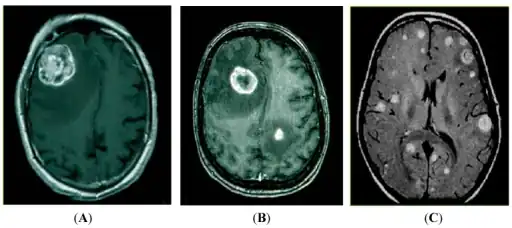

a-c)Magnetic resonance imaging (MRI) detection of brain metastasis

Brain metastasis in the right cerebral hemisphere from lung cancer shown on T1-weighted magnetic resonance imaging with intravenous contrast.

Brain imaging (neuroimaging such as CT or MRI) is needed to determine the presence of brain metastases.[5] In particular, contrast-enhanced MRI is the best method of diagnosing brain metastases, though detection is primarily done by CT.[9] Biopsy is often recommended to confirm diagnosis.[5]

In brain metastasis due to malignant melanoma, MRI imaging showed high T1 and low T2 intensity due to the deposition of melanin in the brain. In susceptibility weighted imaging (SWI), it usually shows abnormal SWI hypointensity in larger proportion than brain metastasis caused by breast carcinoma.[11]